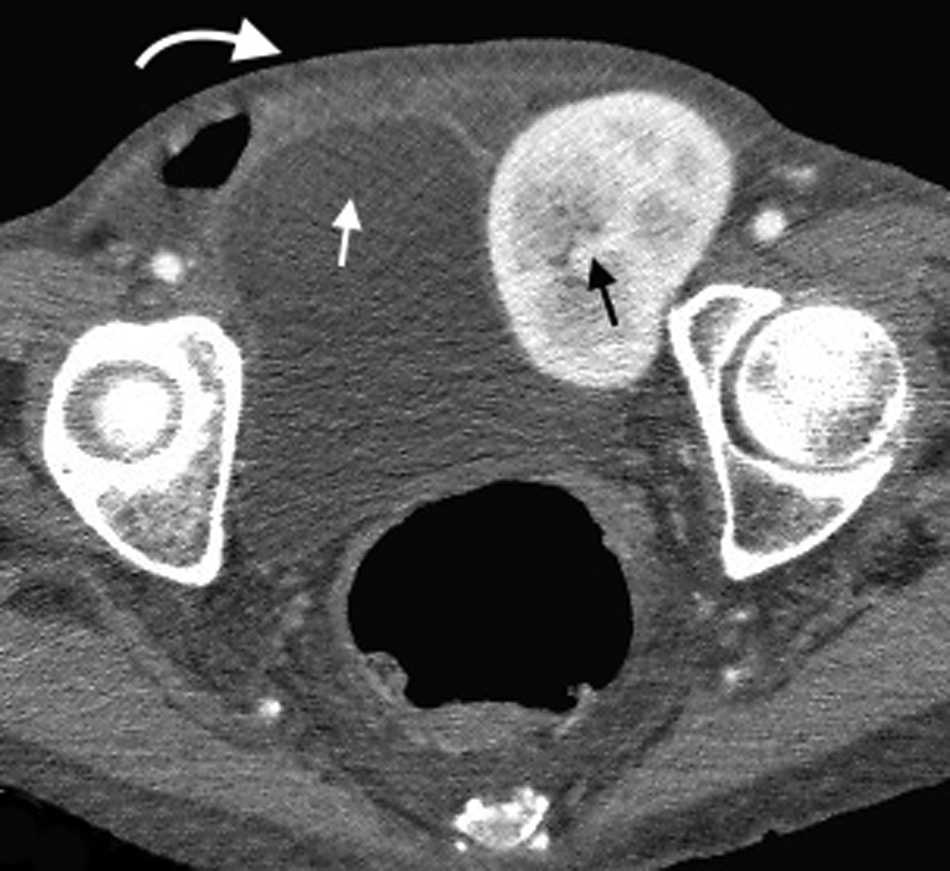

Es una hernia ventral adquirida poco frecuente4. Ocurre por un defecto en la aponeurosis de los m??sculos oblicuo interno y transverso abdominal, y tiene una localizaci??n caracter??stica en la uni??n de las l??neas semilunar y semicircular o arqueada3. Es lateral al recto anterior del abdomen e inferior al ombligo, y casi siempre se encuentra justo por encima del punto en el que los vasos epig??stricos inferiores perforan la pared posterior de la vaina del m??sculo recto del abdomen1.

Su diagn??stico cl??nico no es f??cil porque esta hernia se extiende entre las capas musculares o fasciales de la pared abdominal anterior. El orificio herniario puede ser peque??o, dif??cil de localizar y tener grasa omental (fig. 5a), asas de intestino delgado (fig. 5b) o implantes metast??sicos12 (fig. 6).

El contenido est?? relacionado con los diferentes sitios de debilidad de la pared. A nivel epig??strico se encuentra una herniaci??n del antro g??strico, del l??bulo hep??tico izquierdo (fig. 14) o de la ves??cula biliar (fig. 15). Por su parte, dentro de las umbilicales puede haber grasa peritoneal, asas intestinales, implantes metast??sicos (n??dulo de la hermana Mar??a Jos??) (fig. 16) o l??quido asc??tico (fig. 17). En la hernia de Spiegel suele visualizarse grasa y asas intestinales, mientras que las obturatrices muchas veces son descubiertas porque el paciente presenta un cuadro de obstrucci??n intestinal mec??nica que ayuda al diagn??stico. En cuanto a la lumbar, se puede herniar grasa, el polo renal o el l??bulo hep??tico derecho (fig. 18). En el caso de la inguinal, esta tiene un contenido muy variado, aunque la grasa peritoneal y las asas son los m??s frecuentes (fig. 19). Adem??s, puede herniar ??rganos intrapelvianos, como la vejiga (cistocele) (fig. 20) o el ap??ndice (hernia de Amyand)20 (fig. 21), y si se produce la herniaci??n del ap??ndice dentro del canal crural, se denomina hernia De Garengeot9 (fig. 22). Finalmente, en las eventraciones se observan asas de intestino delgado y grueso, ri??ones trasplantados (fig. 23) y vejigas (fig. 24).